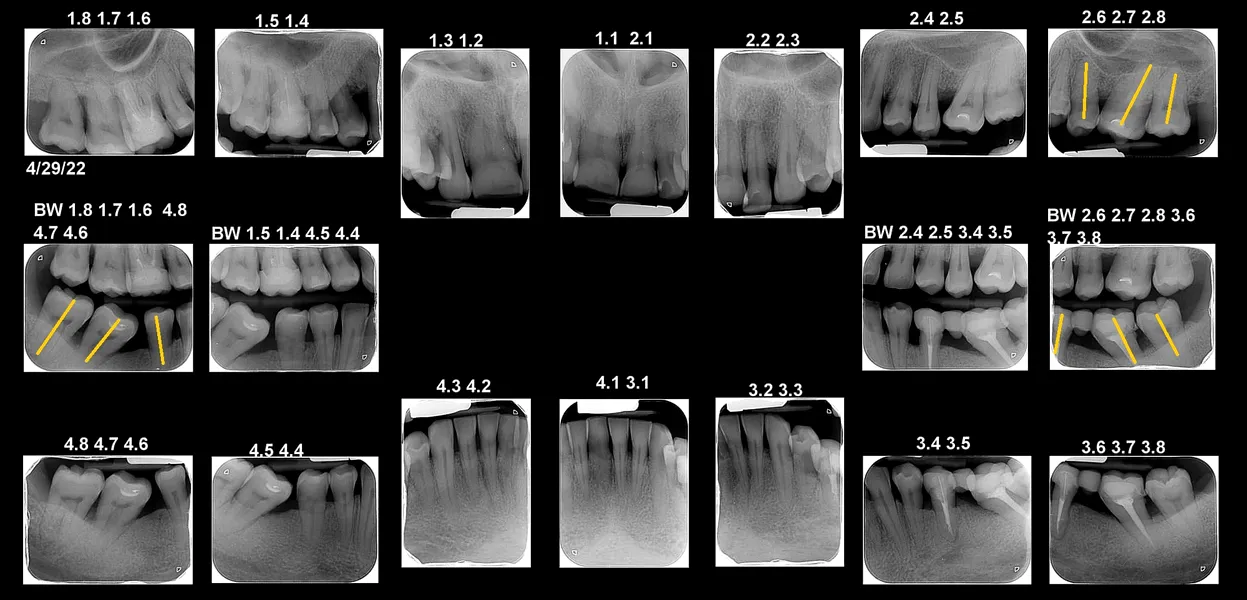

Când dinții nu mai stau la locul lor: de ce uneori ortodonția e esențială înainte de o lucrare dentară